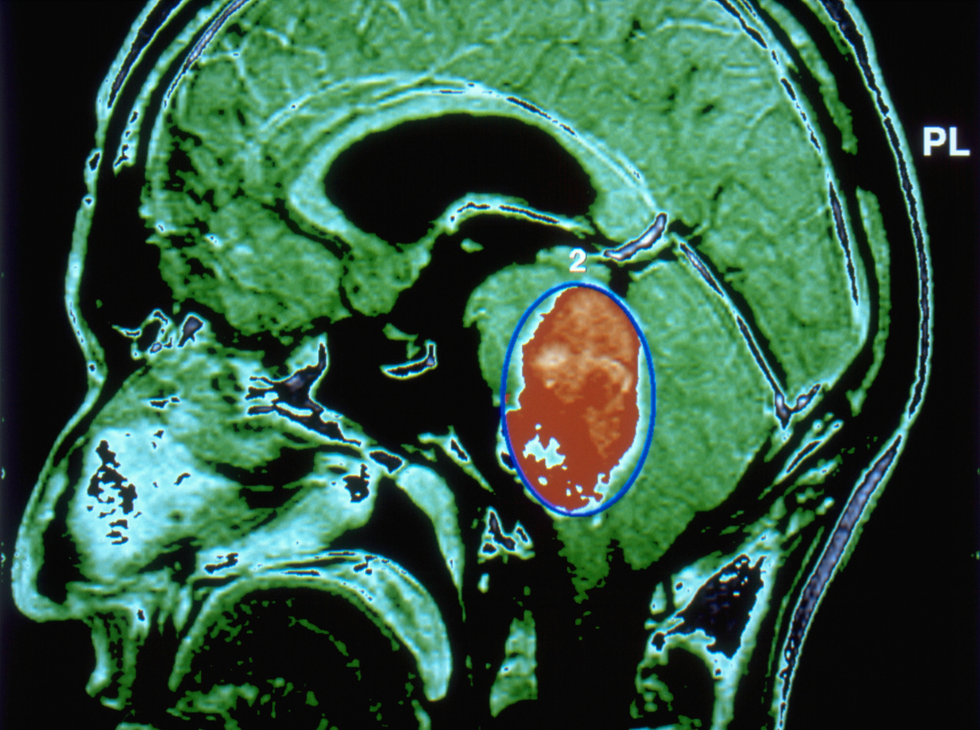

New mRNA vaccine attacked lethal brain tumour within 48 hours of being administered in the first human trial

The first human trial of a personalised brain cancer jab activated the immune system to attack the most lethal and aggressive form of the disease.

The mRNA vaccine, tested on just four patients, triggered a strong immune response to fight malignant glioblastoma within 48 hours of being administered.

Senior author Elias Sayour, a UF Health paediatric oncologist who pioneered the vaccine, said: “In less than 48 hours, we could see these tumours shifting from what we refer to as ‘cold’ – immune cold, very few immune cells, very silenced immune response – to ‘hot’, very active immune response.

“That was very surprising given how quick this happened, and what that told us is we were able to activate the early part of the immune system very rapidly against these cancers, and that’s critical to unlock the later effects of the immune response.”

Glioblastoma has an average survival of around 15 months, and the current standard of care involves surgery, radiation and some combination of chemotherapy.